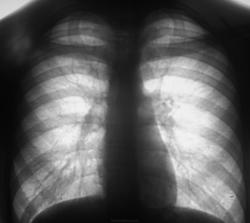

Гражданин "по линии военкомата". Какие будут мнения? Флюорограмма.

Жалоб нет. Кровь в норме. При просмотре флюорограмм, просто "глаз зацепился", возможно зацепился интуитивно. Подсказок нет.

справа  в S1 усиление легочного рисунка

имеется связь с корнем

или в корне что-то, левом

всем здравствуйте) очень не нравиться левый корень, какой то он полицикличный, контакт с туберкулёзом у данного пациента был?

Ваш "гражданин" очень нуждается в дообследовании-верхушечный узор явно асимметричен, над правой ключицей просматриваются очаговые тени. Парень молодой, жалоб может не предявлять (не срабатывает клавиша твердого знака), а пропустить ТВС можно легко. Во всяком случае пока военкомат на какое-то время может о нем забыть.

А может то справа шейное ребро?

Поставил бы норму. Левый корень имеет специфическую структуру. За экраном сразу будет видно, что сосудистый рисунок

в левой верхушке вызывает прежде свего тревогу. Вспышка туберкулеза.

И по сравнению с тем что было очагов справа на верхушке значительно больше стало. Сейчас коллега фтизиатр вплотную им занялся, в областную "контору" пациент направлен. Коллега фтизиатр уже и о КТ в ОПТД договорился.

Тогда странно, что так долго зрел Ваш "гражданин". Целый год при довольно активных нагрузках ТВС вспыхнул бы сильнее, может у парня другое-саркаидоз, например,а?